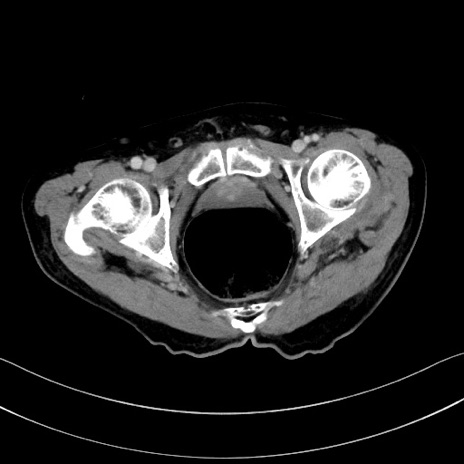

症例28(横断像)

【症例】60歳代男性

【主訴】嘔吐

【現病歴】胃癌にて胃全摘後。食思不振が悪化し、夜中に嘔吐することがある。

【既往歴】胃癌、胃全摘、脾摘、胆摘後

【データ】WBC 5900、CRP 10.56